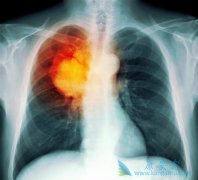

• 什么是肺癌化疗?小细胞肺癌化疗时要注意些什么?

什么是肺癌化疗?小细胞肺癌化疗时要注意些什么?

肺癌是日常生活中常见的一种癌症,而化疗是治疗肺癌的一种常用手段,那么患者什么情况下需要 肺癌化疗 ?化疗时有哪些注意事项呢?下边小编就为大家介绍下与肺癌化疗相关的问题。肺癌化疗是化学药物治疗肺癌的简称,是利用化学药物组织癌细胞增殖、浸润 ...